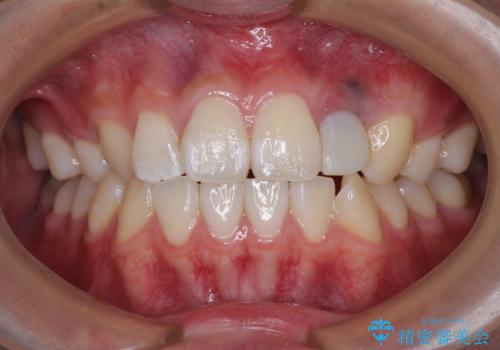

抜歯と言われた前歯 牽引してセラミッククラウンで保存する

- 他院で前歯の抜歯が必要と言われたとのことで来院された患者様です。

過去にぶつけたことで神経組織が壊死してしまったようで、その後むし歯が進行して歯肉深いところにまで進んでいる状態でした。

まずは部分矯正により歯を牽引し、歯肉や歯槽骨の位置を調整するために歯周外科処置を行い、治癒を待ってオールセラミッククラウンにて補綴治療を行うこととしました。

しっかりとむし歯を牽引したことで、クラウンの周りの腫れが引き、自然な口元に仕上げることができました。